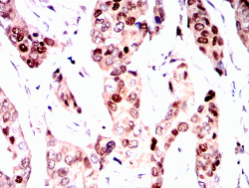

PGR Mouse Monoclonal antibody[2C11F]

PGR: progesterone receptor. This gene encodes a member of the steroid receptor superfamily. The encoded protein mediates the physiological effects of progesterone, which plays a central role in reproductive events associated with the establishment and maintenance of pregnancy. This gene uses two distinct promotors and translation start sites in the first exon to produce two isoforms, A and B. The two isoforms are identical except for the additional 165 amino acids found in the N-terminus of isoform A only, and mediate their own response genes and physiologic effects with little overlap. The location of transcription initiation for isoform B has not been clearly determined.

Immunogen:    Purified recombinant fragment of PGR (aa731-909) expressed in E. Coli.

IHC    1/200 - 1/1000